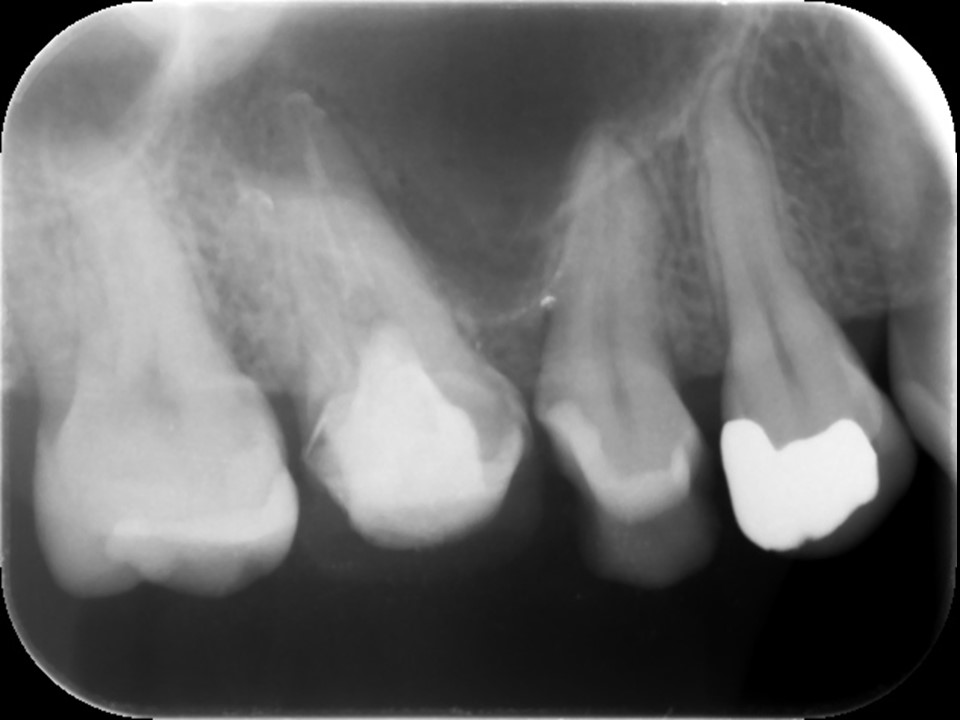

初診時CT画像。上顎洞に当該歯の部位に一致するX線不透過性の亢進を認める。繰り返し根管治療を行ったためか、根尖部は破壊されて太く開いている。また、湾曲した根管を何度も治療を行ったため、根尖部のパーフォレーションを認めた。

同CT画像。上顎洞のX線不透過部は消失し、上顎洞炎が治癒しているのが分かる。